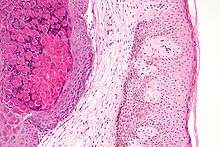

The Molluscum contagiosum virus (MCV) is a species of virus in the poxvirus family, which causes the disease Molluscum contagiosum in humans. Virions have a complex structure and is consistent with the structure of the poxvirus family: a surface membrane, a core, and lateral bodies. Virus may be contained within inclusion bodies and mature by budding through the membrane of the host cell giving rise to a large amount of viral shedding in a short period of time. Approximate measurements of the virus are 200 nm in diameter, 320 nm in length and 100 nm in height.[1]

Diagnosis is made on the clinical appearance; the virus cannot routinely be cultured. The diagnosis can be confirmed by excisional biopsy. There are 4 types of MCV, MCV-1 to -4. MCV-1 is the most prevalent in human infections, and MCV-2 seen usually in adults and often sexually transmitted.[2][3][4] Polymerase chain reaction techniques are being developed to help confirm lesions as being caused by MCV,[5] and distinguish between strains.[6][7]